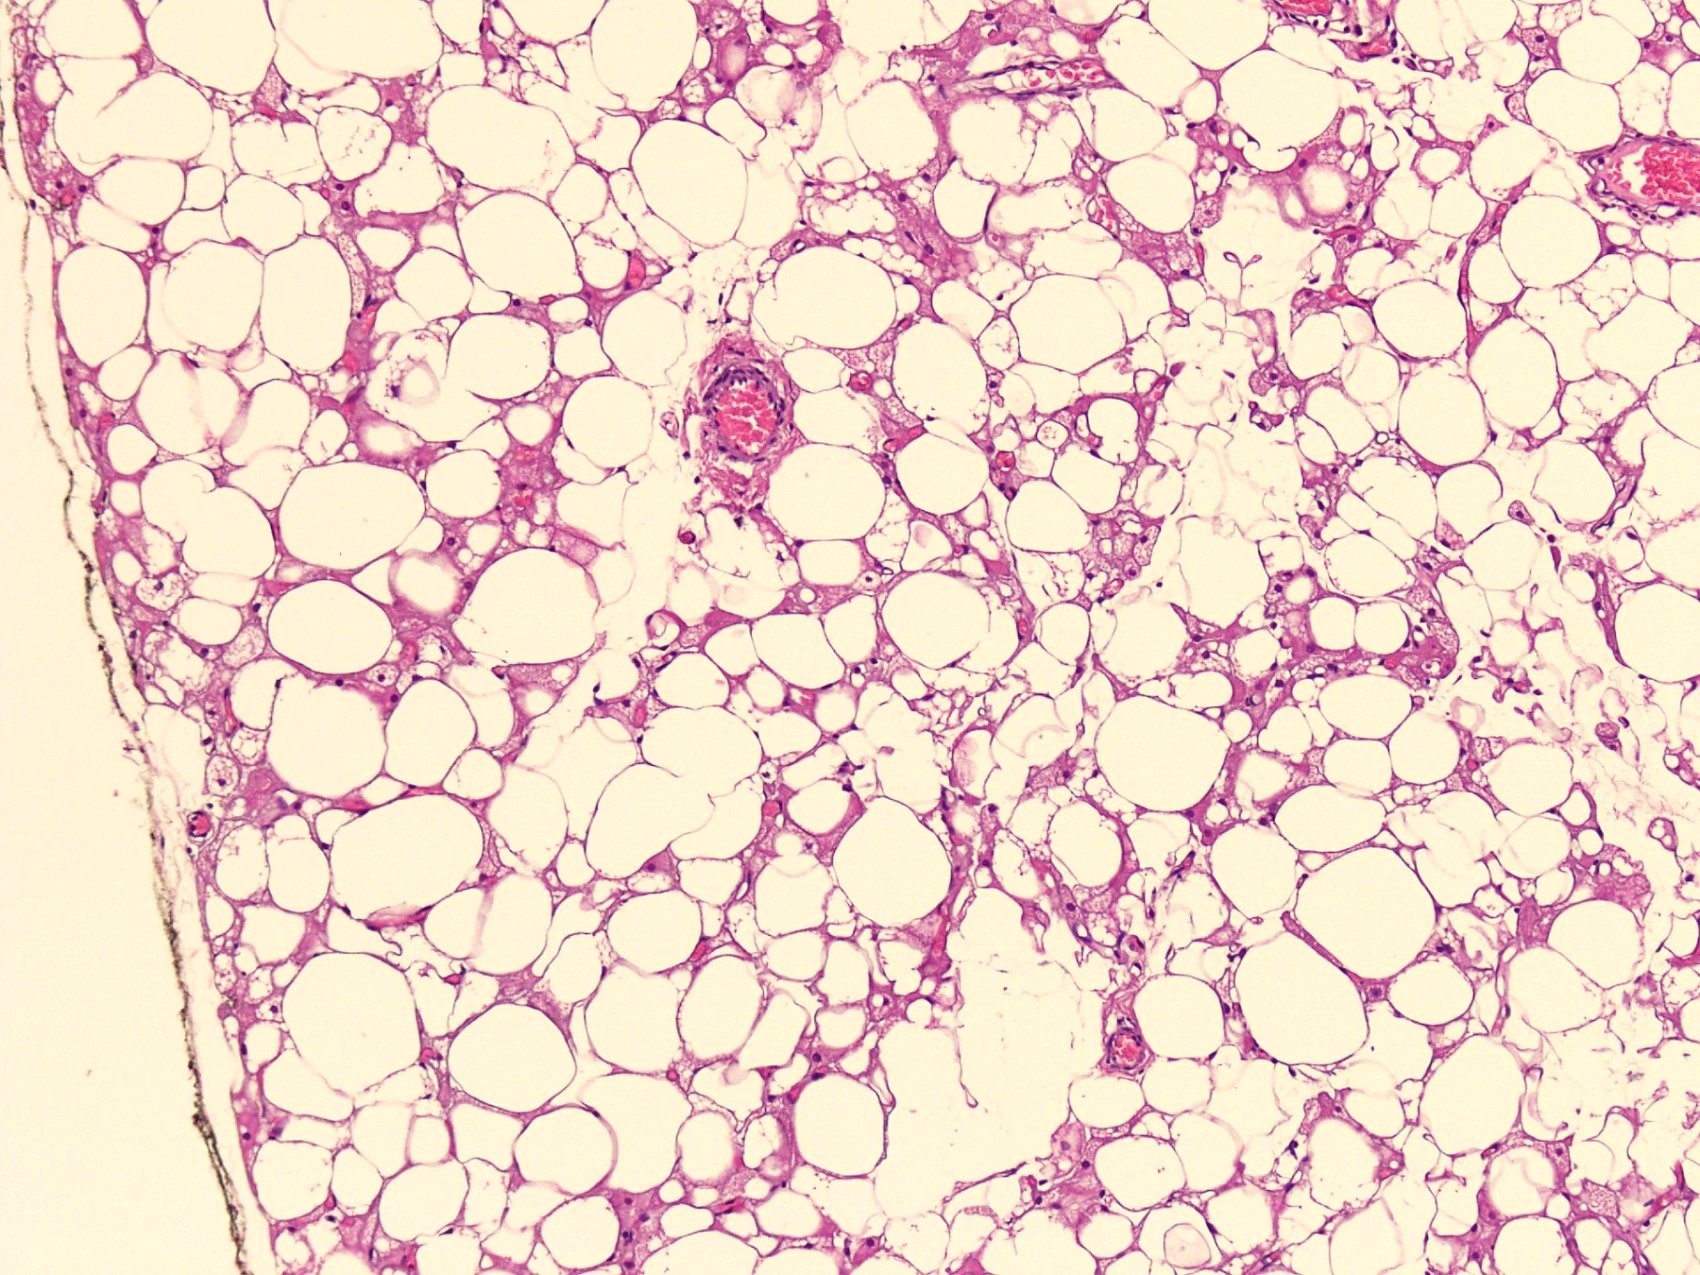

Microscopic (histologic) description

- Neoplastic lesion composed of polygonal brown fat cells with stromal cells in the background (Case Rep Oncol 2017;10:438)

- Large number of pale and eosinophilic brown fat cells with multivacuolated, eosinophilic granular cytoplasm and small central nucleus (about 70%) admixed with variable amount of univacuolated white cells (Case Rep Oncol 2017;10:438, Am J Case Rep 2020;21:e921447, J Comput Assist Tomogr 2019;43:793, J Pathol Transl Med 2017;51:499, Am J Surg Pathol 2018;42:951, Virchows Arch 2021;478:527)

- Multivacuolations resemble lipoblasts

- Morphological variations or subtypes: typical, myxoid (9%), lipoma-like (7%), spindle cell (2%), thick bundles of collagen fibers, presence of mast cells and exclusively containing brown fat cells (Case Rep Oncol 2017;10:438, Am J Case Rep 2020;21:e921447, Virchows Arch 2021;478:527)

- Cytological atypia, necrosis and mitosis is unusual (J Pathol Transl Med 2017;51:499, Am J Surg Pathol 2018;42:951, BMC Surg 2021;21:30)

Microscopic (histologic) images